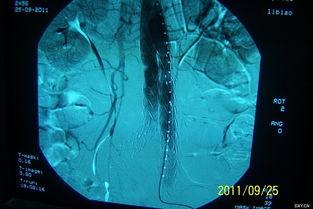

主动脉支架,听起来是不是很专业?没错,它是一种用于治疗主动脉夹层的医疗器械。主动脉夹层是一种严重的血管疾病,如果不及时治疗,后果不堪设想。而国产主动脉支架,就是用来修复受损的主动脉,防止病情恶化的“救星”。

这个国产主动脉支架的视频,让我对它有了更深入的了解。首先,它采用了先进的3D打印技术,可以根据患者的具体情况进行个性化定制。这样一来,支架的贴合度更高,治疗效果自然也就更好。

视频中的案例让我印象深刻。有一位名叫李先生的病人,因为主动脉夹层导致生命垂危。在医生的建议下,他选择了国产主动脉支架进行治疗。经过一段时间的恢复,李先生的病情得到了明显改善,生活也恢复了正常。